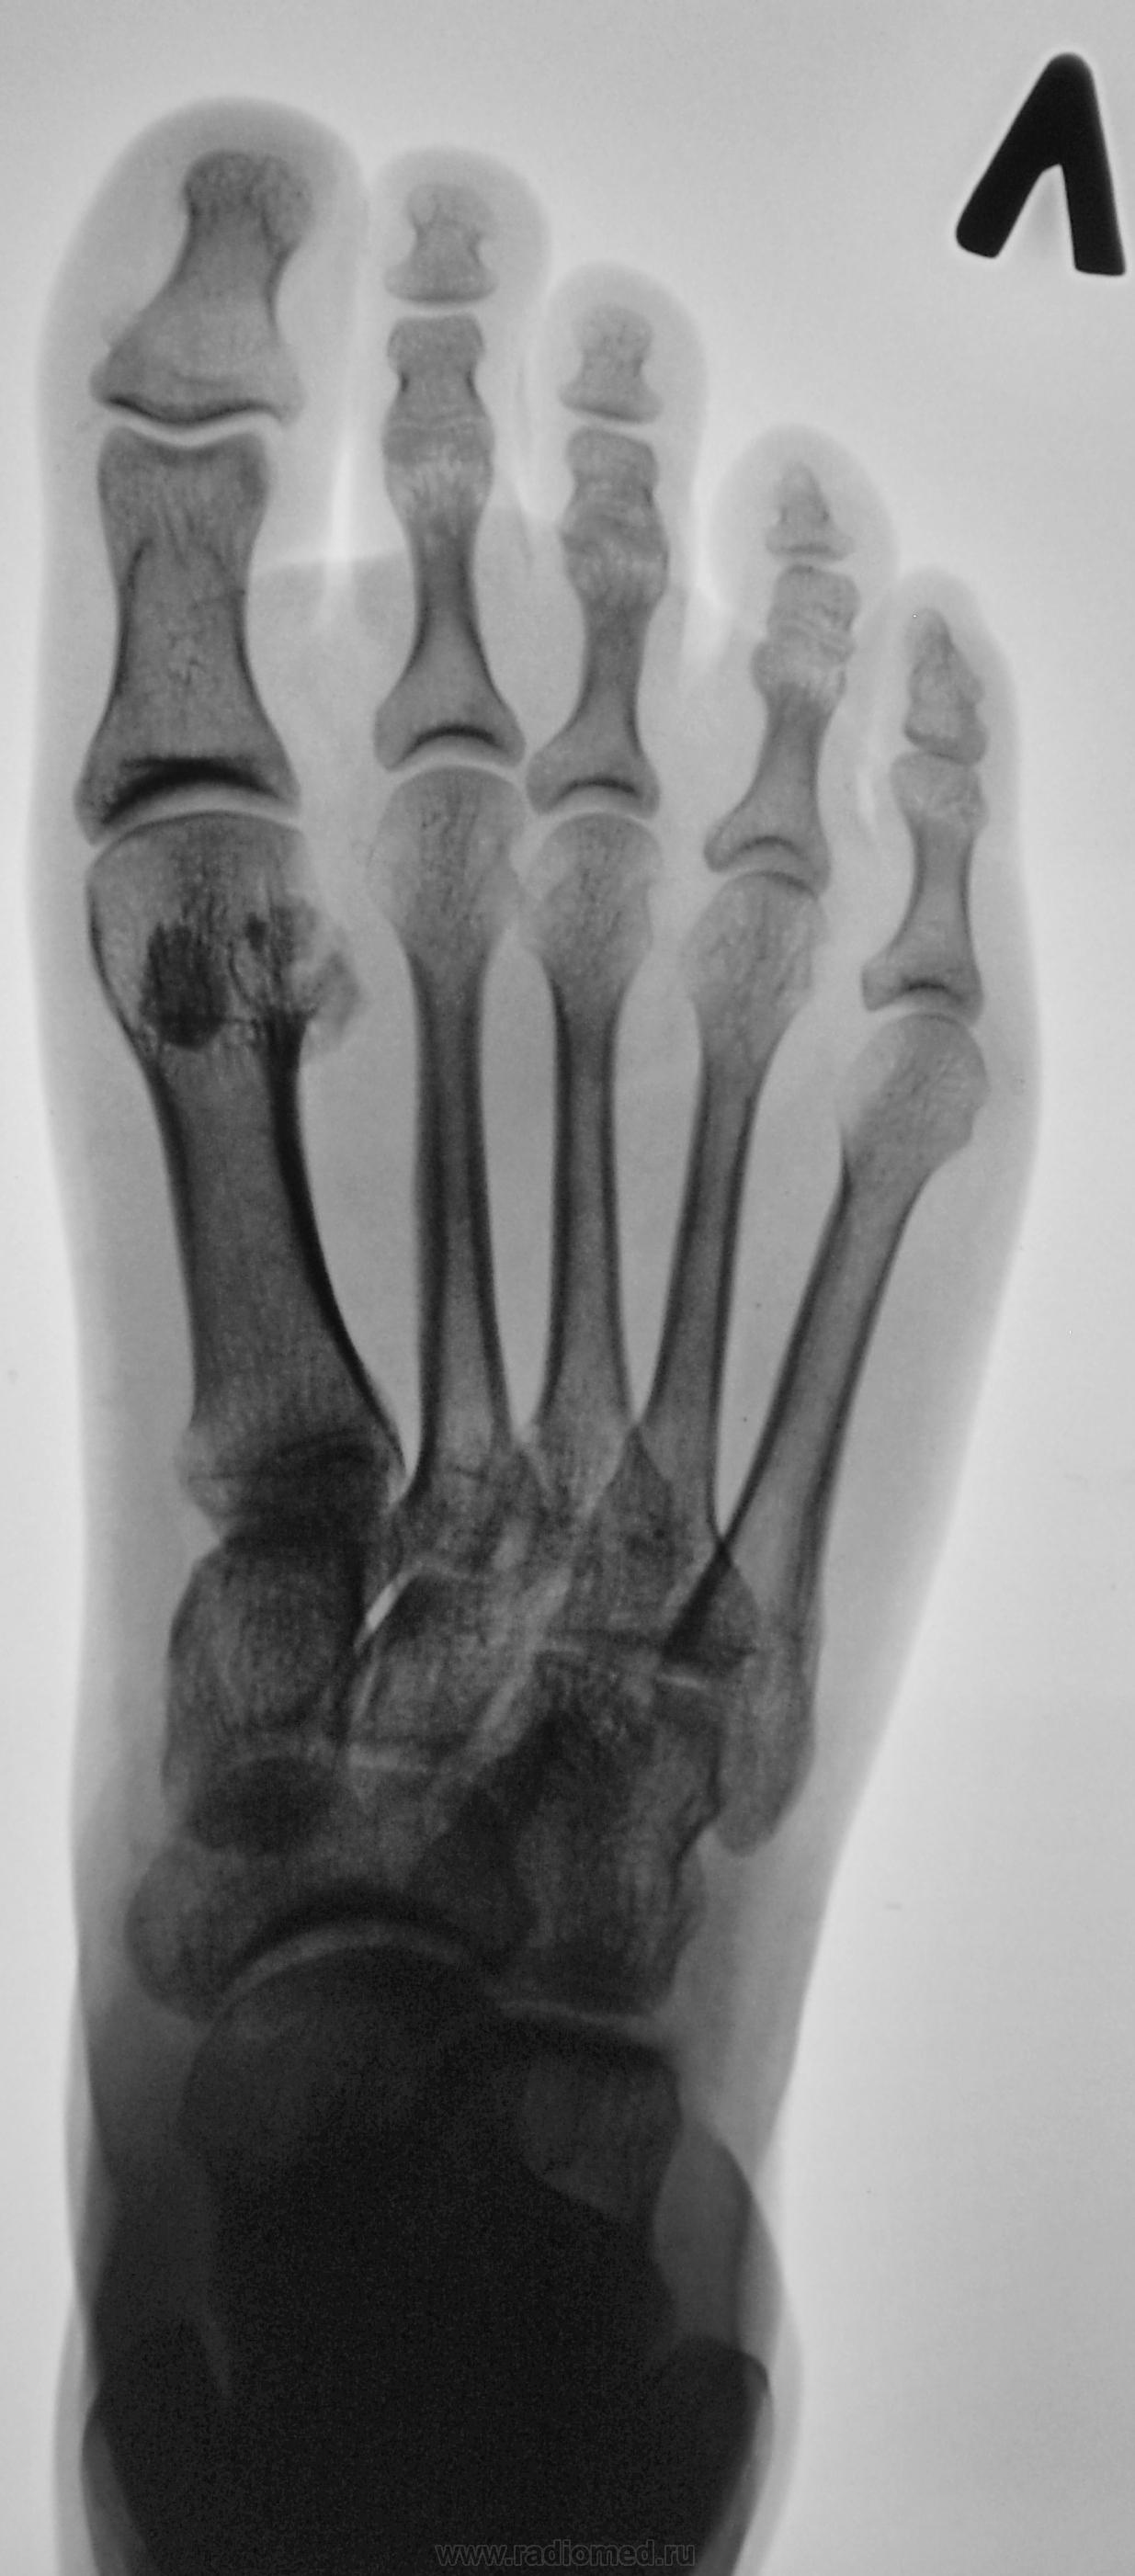

Молодая женщина. Беспокоят боли в ступнях по подошвенной поверхности, больше слева.

Правая стопа сделана больше для сравнения.

Остеохондропатия сесамовидной кости 1 пл/фал.сустава левой стопы.

Весьма патогномоничной является рентгенологическая картина третьей стадии заболевания - стадии фрагментации. Пораженный отдел кости уже не дает гомогенной тени, а состоит из нескольких темных бесструктурных изолированных фрагментов неправильной формы. Светлые участки, на фоне которых видны эти фрагменты, соответствуют разрастаниям соединительной ткани и хряща между некротическими массами. Высота пораженного отдела кости уменьшается. Длительность третьей стадии составляет от полугода до двух с половиной лет, а иногда и более. Вероятно Валентин Львович, дама не сидит, а ходит, постоянная нагрузка веса тела делает свое дело.

Фрагменты с увеличением.

"На рентгенограмме-типичная дезорганизация структурного рисунка несколько иногда увеличенной косточки с фрагментацией её тени.Регенеративные явления выражены незначительно,полного восстановления стуктуры не бывает"-С.А.Рейнберг т2 стр286.      (несколько иногда( в тексте))-это вероятно в данном случае.

Правую никак не смог разглядеть надо бы обработать получше. в левой старая связочная травма сустава Шопара, постттравматический небольшой подвывих пяточно-кубовидного сустава, следы почившего гемартроза там же. Травма эта не с лестницы вперед упала?

несросшийся перелом сесамовидной слева